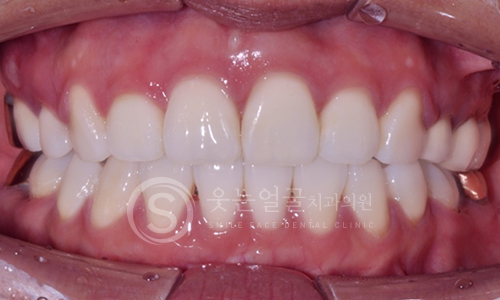

한눈에 보는

임플란트 전후사진